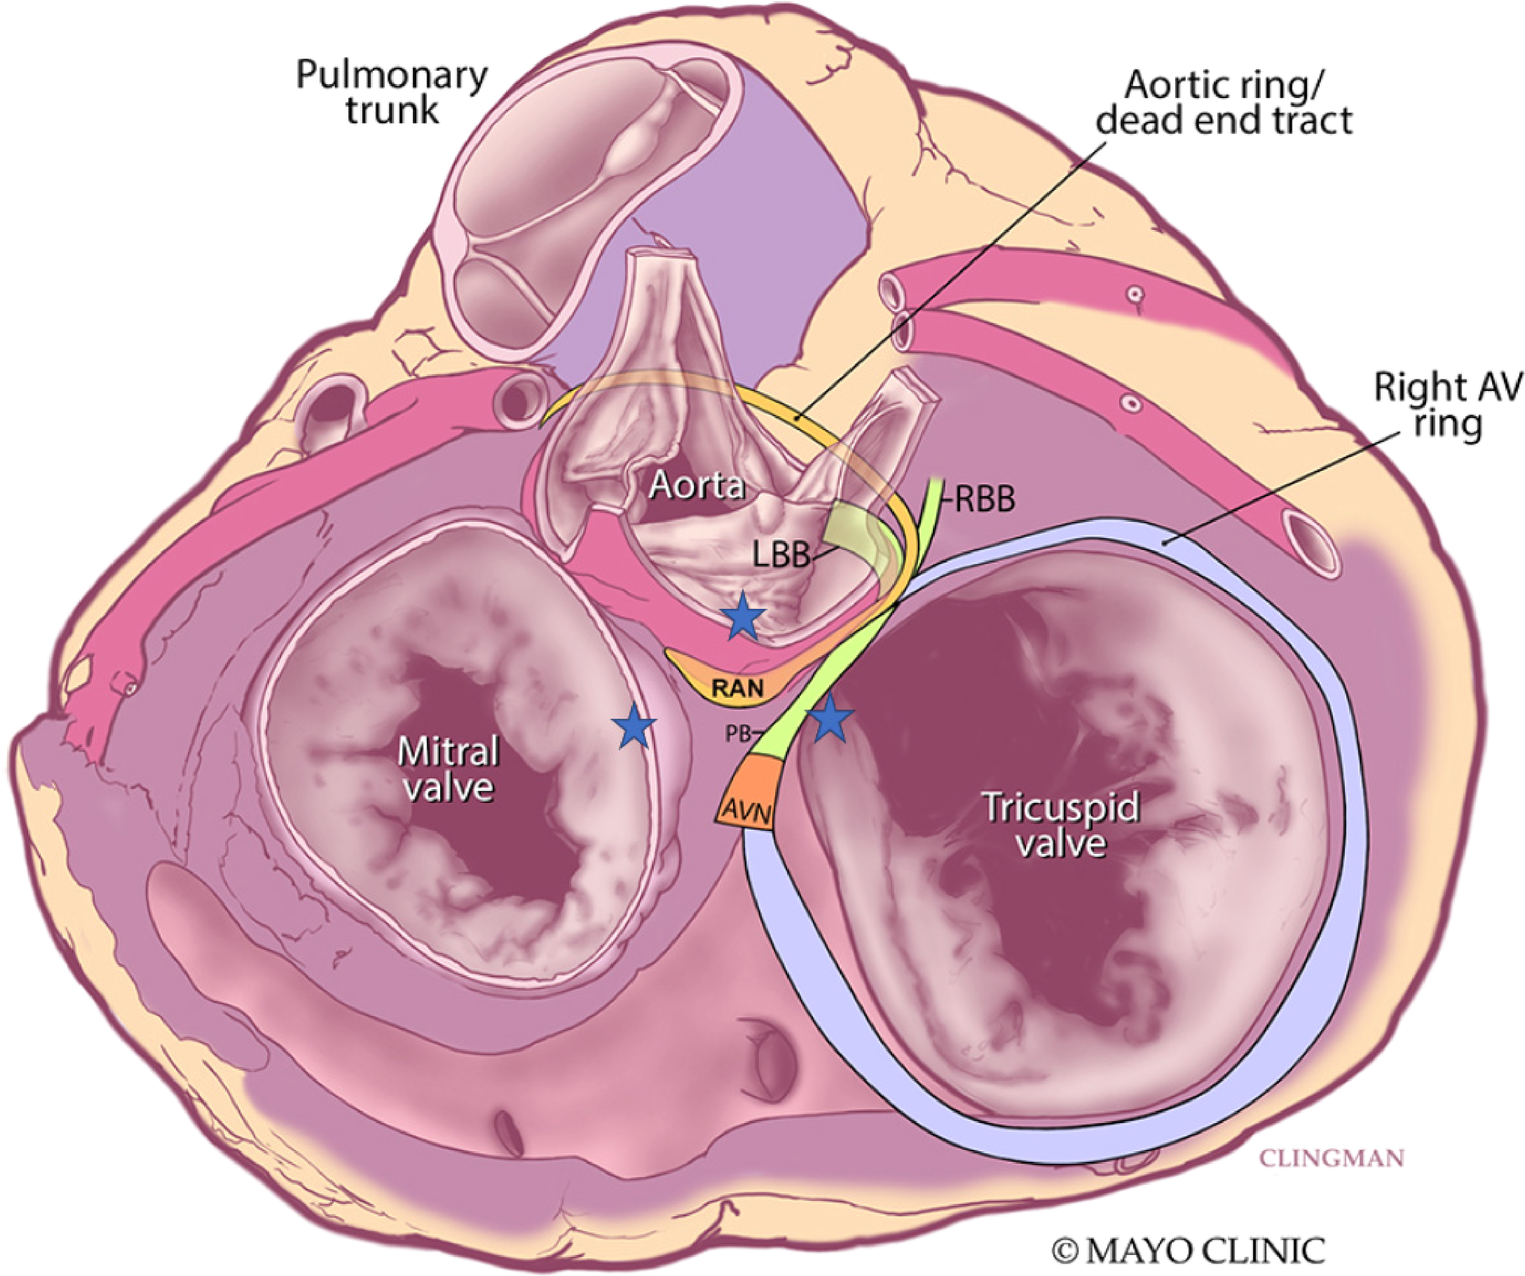

Figure 4

Superior view of the retroaortic node (RAN) and neighboring structures. Star represents vantage points of ablation to the area. AVN, atrioventricular node; PB, penetrating bundle; RBB, right bundle branch; LBB, left bundle branch. Adapted from Yanni et al. (14).

Despite some clinical and animal studies on arrhythmias arising from the interatrial septum, little attention has been placed on the arrhythmogenic role of the RAN, a large remnant of the “atrioventricular (AV) ring” in the atrial septum. The AV rings and RAN are thought to be remnants of the AV canal. The RAN is composed of cardiomyocytes and is separated from the AV node by the antero-superior rim of the fossa ovalis and from the bundle of His by the membranous septum (9, 10). Its location within the antero-superior interatrial wall means that it does have potential continuity with the transitional cells of the AV node but is distinct from the compact node itself (9) (Figure 4).

Electrophysiologic and molecular investigations of the RAN in animal studies suggest similar gene expression and ion channels as the compact AV node and point to its ability to serve as an ectopic source of ATs (11). Small clinical studies corroborate this notion with observations such as prompt termination of tachycardia with intravenous adenosine before production of AV block. In one such series of 43 patients, Bahora et al. (9) found all tachycardias (35/35) which were tested were found to be adenosine sensitive; the authors commented that this early termination was suggestive that the arrhythmic focus consists of node-like tissue but is distinct from the AV node itself. Clinical reports also suggest that the RAN may not respond to stress heating from radiofrequency ablation with automaticity (9, 12, 13). For ATs originating from this area, the right atrium offers a reasonable approach for ablation, although sometimes lesions need to be created from contiguous areas to “sandwich” the arrhythmic focus. The anterosuperior border of the fossa ovalis is marked by the non-coronary sinus of Valsalva and offers another vantage point for the proceduralist to approach perinodal ATs, including those tachycardias where the RAN may be implicated. While approaches from the right atrium and non-coronary sinus of Valsalva are well documented (12, 13), transeptal access and ablation of the left atrial septum must be considered in some patients where the septum is thicker, contact is not ideal, or atrial electrograms are not as early from the non-coronary sinus of Valsalva (Figure 4). In our case, ablation lesions were created from all three vantage points.